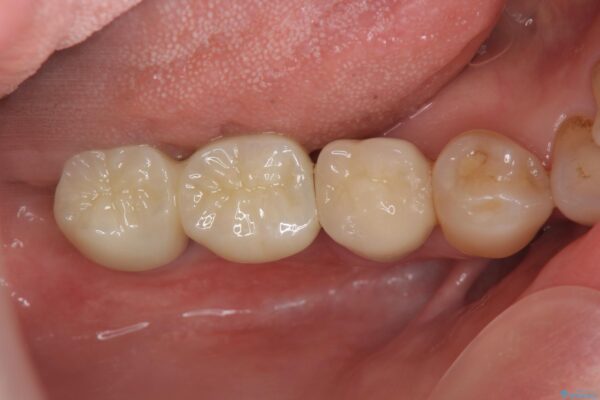

治療後

奥歯から膿のにおいがする インプラントによる機能回復 治療後画像 奥歯から膿のにおいがする インプラントによる機能回復 治療後画像 奥歯から膿のにおいがする インプラントによる機能回復 治療後画像 奥歯から膿のにおいがする インプラントによる機能回復 治療後画像

治療を終えて

歯は大きな力がかかると割れてしまうことがよくあります。

破折した歯はほとんどの場合抜歯が必要になることが多く、インプラントを用いた咬合機能の回復は、また噛めるようになるだけでなく残っているその他の歯を守る意味でも非常に大きな意味を持ちます。